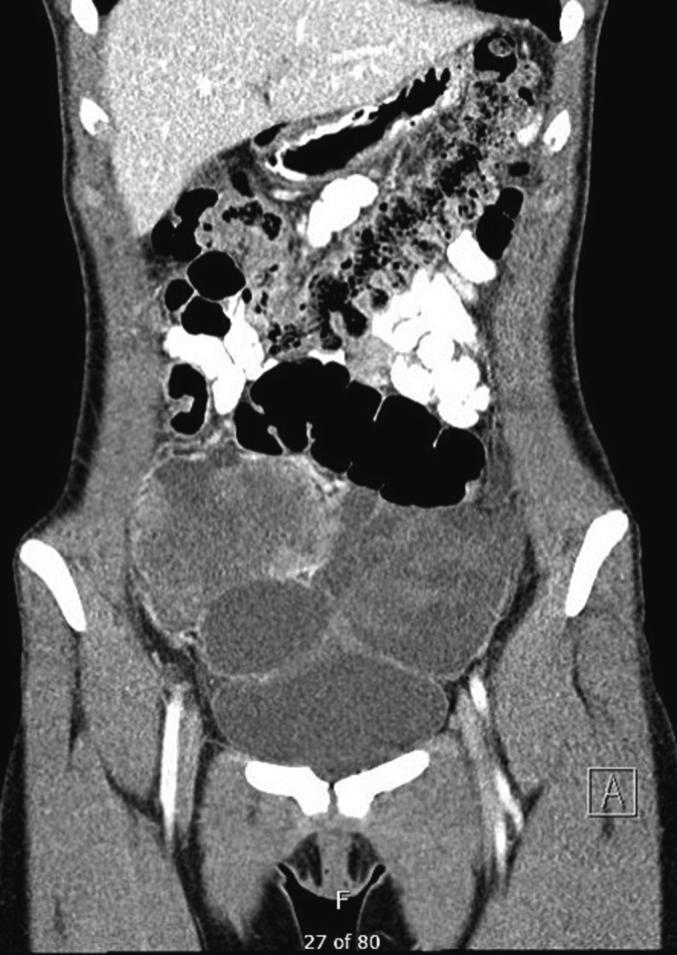

syndrome is a rare genetic disorder predisposing young patients to multiple types of cancer. A 17-year-old woman with a history of mixed Sertoli-Leydig cell tumor and juvenile granulosa cell tumor of the left ovary at age 14 presented with a pelvic mass. She underwent fertility preservation cytoreductive surgery and the pathology showed high-grade sarcoma with rhabdomyosarcomatous differentiation. After the surgery, patient received one cycle of chemotherapy but her disease continued to progress. She therefore underwent total hysterectomy, right salpingo-oophorectomy and hyperthermic intraperitoneal chemotherapy followed by consolidation chemotherapy. Magnetic resonance imaging revealed no evidence of the disease before and after the completion of her chemotherapy. Genetic testing confirmed the pathogenic variant. However, she presented again with a recurrence of the disease 6 months later and ultimately died of the disease 11 months after the surgery. Our case demonstrates the challenging management of this rare disease in a young patient and the need for new and effective treatments.

该综合征是一种罕见的遗传性疾病,易使年轻患者患多种类型的癌症。一名17岁女性,14岁时曾患左卵巢混合性支持-间质细胞瘤和幼年型颗粒细胞瘤,现出现盆腔肿块。她接受了保留生育功能的减瘤手术,病理显示为高级别肉瘤,伴有横纹肌肉瘤分化。手术后,患者接受了一个周期的化疗,但疾病仍继续进展。因此,她接受了全子宫切除术、右侧输卵管卵巢切除术和热灌注化疗,随后进行巩固化疗。磁共振成像显示化疗完成前后均无疾病证据。基因检测证实了致病变异。然而,6个月后她疾病再次复发,最终在手术后11个月死于该疾病。我们的病例表明了在年轻患者中管理这种罕见疾病具有挑战性,并且需要新的有效治疗方法。